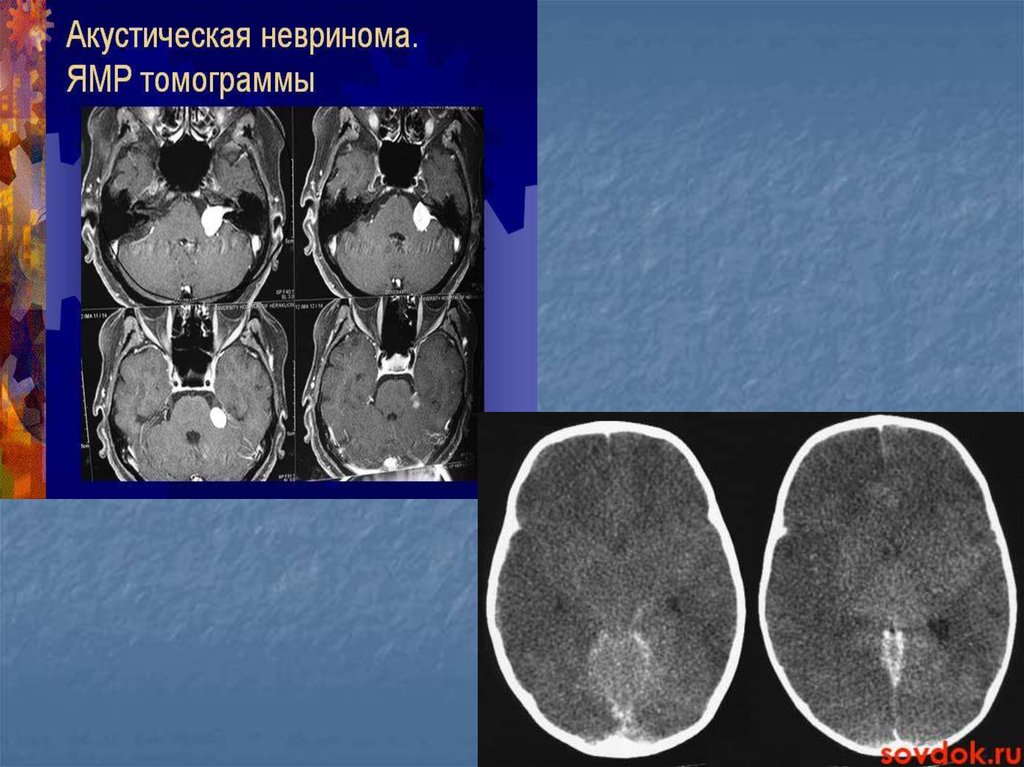

19. Показания

При заболеваниях головного мозга показания к МРТ следующие:

инфаркты, инсульты – для оценки масштабов поражения мозга;

рассеянный склероз; дегенеративные и демиелинизирующие патологии

нервной ткани; нарушения работы гипофиза; инфекционные

заболевания (энцефалит и пр.)

23. Показания

Опухоли различной локализации

Эпилепсия(определения очага)

Травмы головного мозга

Сосудистые нарушения головного мозга

Деменции